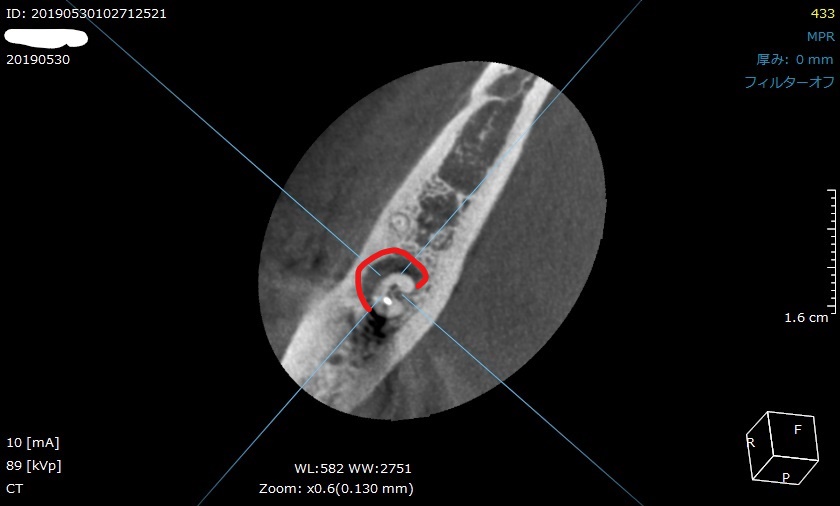

CT撮影の画像です。

CT撮影は、様々な方向から歯を立体的に確認することができます。

つまり3Dですね。

輪切り方向から見ても、

正面から見ても、赤枠の場所が黒く抜けています。

CT撮影で、膿んで骨が溶けている範囲が詳細に分かります。